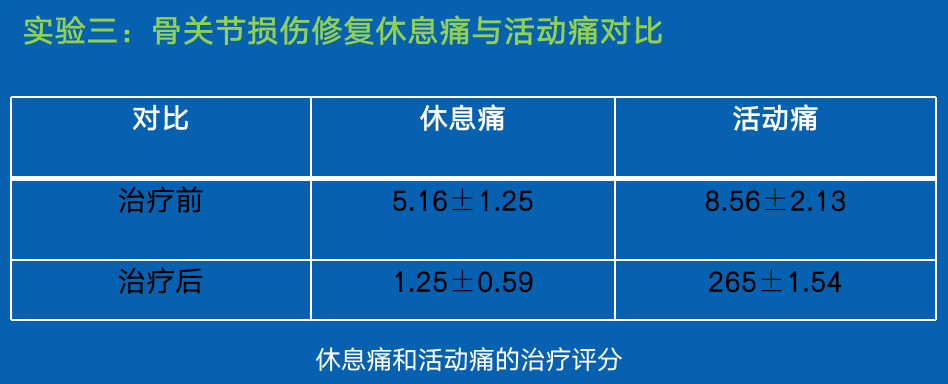

结论:

在连续施用本发明实施例所述组合物后,受体骨关节疼痛症状得到明显缓解,同时骨关节功能也得到改善。